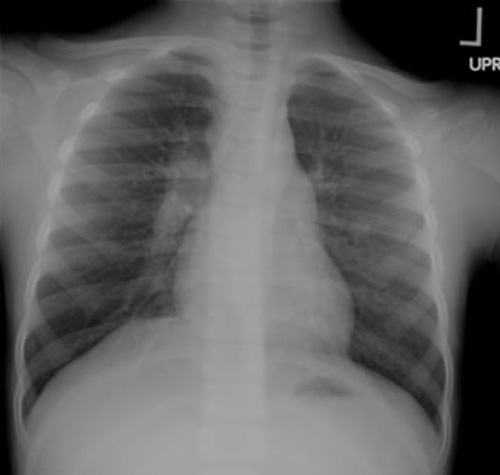

Правосторонняя прикорневая аденопатия у ребенка

Рентгенография грудной клетки - Исследование первой линии при диагностике туберкулеза - Почти всегда отмечаются патологические изменения на рентгенограмме у иммуноскомпроментированных лиц. К типичным изменениям относятся фиброзно-очаговые затемнения в верхних долях с кавернами или без них - Нетипичный легочный рисунок может сопровождаться затемнением в средний или нижних долях, прикорневой или паратрахеальной лимфаденопатией или плевральным выпотом - Специалисты утверждают, что атипичные изменения на рентгенограмме являются скорее следствием иммуносупрессии, чем первичного туберкулеза - ВИЧ статус обуславливает лимфаденопатию, выпот, вовлечение нижних долей легких и милиарный рисунок; при этом каверны обнаруживаются реже. Отметим, что у больных с прогрессирующей ВИЧ инфекцией рентгенограмма может быть нормальной |

- Характерные отклонения при туберкулезе - Нехарактерные отклонения при туберкулезе - Норма |